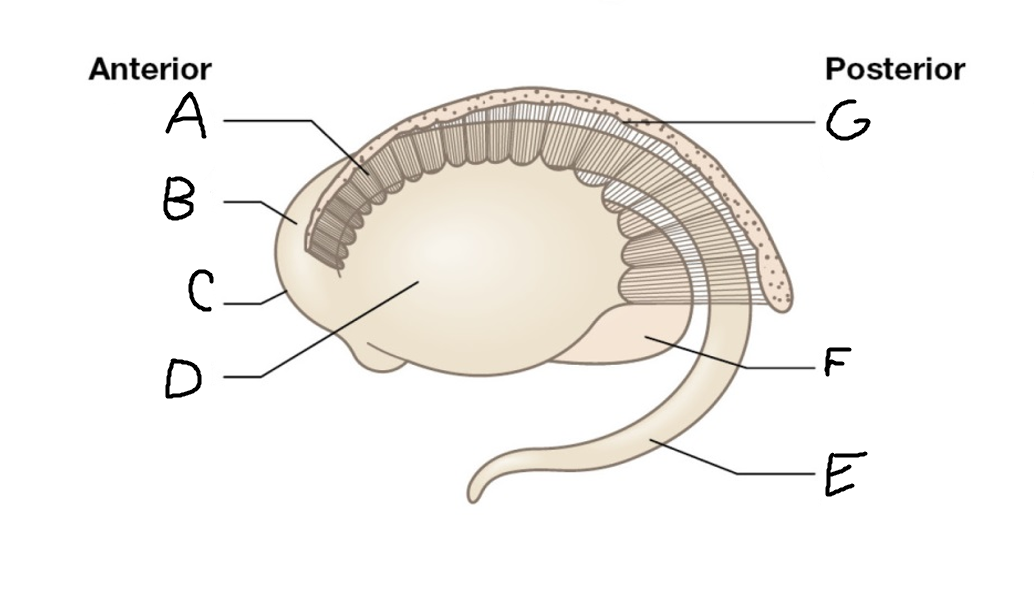

A

head of caudate nucleus

C

putamen

D

external segment of globus pallidus

E

internal segment of globus pallidus

F

third ventricle

G

thalamus